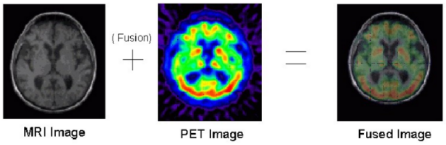

在民用领域,在医学图像分析、安全导航、交通检测等方面都有着重大的应用价值。如图2所示,在医学图像分析上,通过将MRI与PET扫描图像进行融合,可以更好地辅助医生对患者情况做出判断。除此之外,在日常生活中,图像融合还可用于无缝添加原图像所缺失的内容,或通过融合技术进行艺术的在创作,营造出普通摄影无法表达的意境。

图2 图像融合在医疗方面的应用